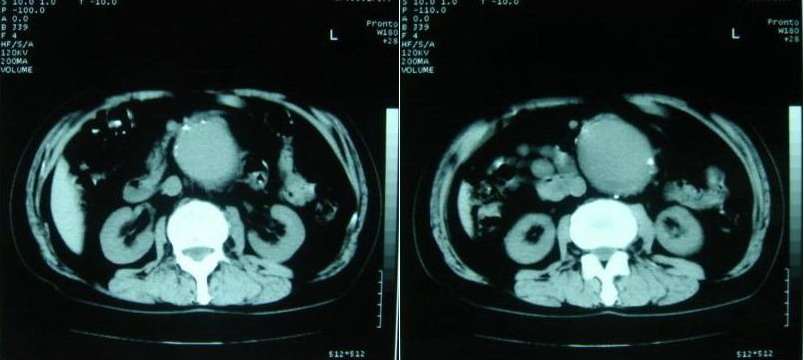

以下是引用zjzjr在2007-8-29 17:09:00的发言:[br]典型腹主动脉瘤累及双侧髂总动脉,建议增强扫描.

以下是引用why7912在2007-8-29 19:08:00的发言:[br]典型夹层动脉瘤,可见真假双腔及附壁血栓

以下是引用借我一双慧眼在2007-8-29 16:24:00的发言:[br]典型腹主动脉瘤累及双侧髂总动脉

以下是引用快乐男生在2007-8-29 16:45:00的发言:[br]腹主动脉及右髂总动脉大范围的管径增粗,[br]管壁多发的钙化,[br]并见真假腔(双腔征),假腔可见附壁血栓.[br]考虑腹主动脉夹层动脉瘤 .建议增强或mri